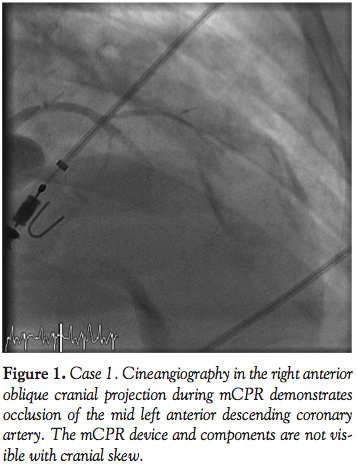

her initial systolic central blood pressure was 50 mm Hg. Left coronary angiography demonstrated occlusive thrombus extending across the length of the left main coronary artery with only TIMI 2 distal flow and minimal movement of the cardiac silhouette (Figure 3). As her hemodynamics continued to deteriorate, manual guide catheter aspiration and guidewire manipulation dislodged the thrombus with minimal thromboembolism to the apical LAD (Figure 4). Her cardiac motion on fluoroscopy

improved, but her blood pressure continued to decline and she required CPR for PEA cardiac arrest. Mechanical CPR was initiated and an IABP was placed via the right femoral artery. Intensive support with mCPR, IABP, and vasopressors provided full support for over 40 minutes as she experienced recurrent PEA and refractory ventricular fibrillation. Angiography during mCPR demonstrated patency of the left coronary artery (Figure 5). After continued support and intravenous lidocaine, her pulse was restored and the mCPR was discontinued. She was alert and responsive, and transferred to the coronary care unit (CCU) with IABP and vasopressor support. The IABP was removed on hospital day 2, although she continued to require inotropic support. Echocardiography demonstrated a normal-sized but severely hypokinetic left ventricle with an ejection fraction <20%. On hospital day 3, she experienced acute mental status changes due to an intracranial hemorrhage and expired on hospital day 4.

Fluoroscopic and cineangiographic imaging during mCPR with the LUCAS device requires few significant adjustments. The images presented here represent one center’s experience and diagnostic images were obtained in all cases. Anterior-posterior projections are limited by the height and radio-opacity of the LUCAS drive unit over the patient’s chest. Straight right and left anterior oblique views provide adequate visualization despite the back-brace component of the device being visible on fluoroscopy. As evidenced in Cases 1 and 4, significant cranial angulation (>30°) can provide coronary imaging without visual encroachment by the device components.

In animal models, cerebral blood flow during CPR is improved with mCPR,15 and mCPR devices provide significantly higher coronary perfusion pressures than manual CPR.16 Coronary flow assessment has been reported in both animal models and human subjects.16,17 In 4 out of 6 patients studied by Larsen et al with TIMI 3 flow during mCPR, invasive measurements documented adequate coronary perfusion pressure gradients. In the present experience, coronary flow during mCPR is pulsatile, but classification by TIMI grade is readily apparent. In Cases 1, 4, and 5, the PCI procedure itself was performed during mCPR compressions (Figures 1, 2, 8, and 10).